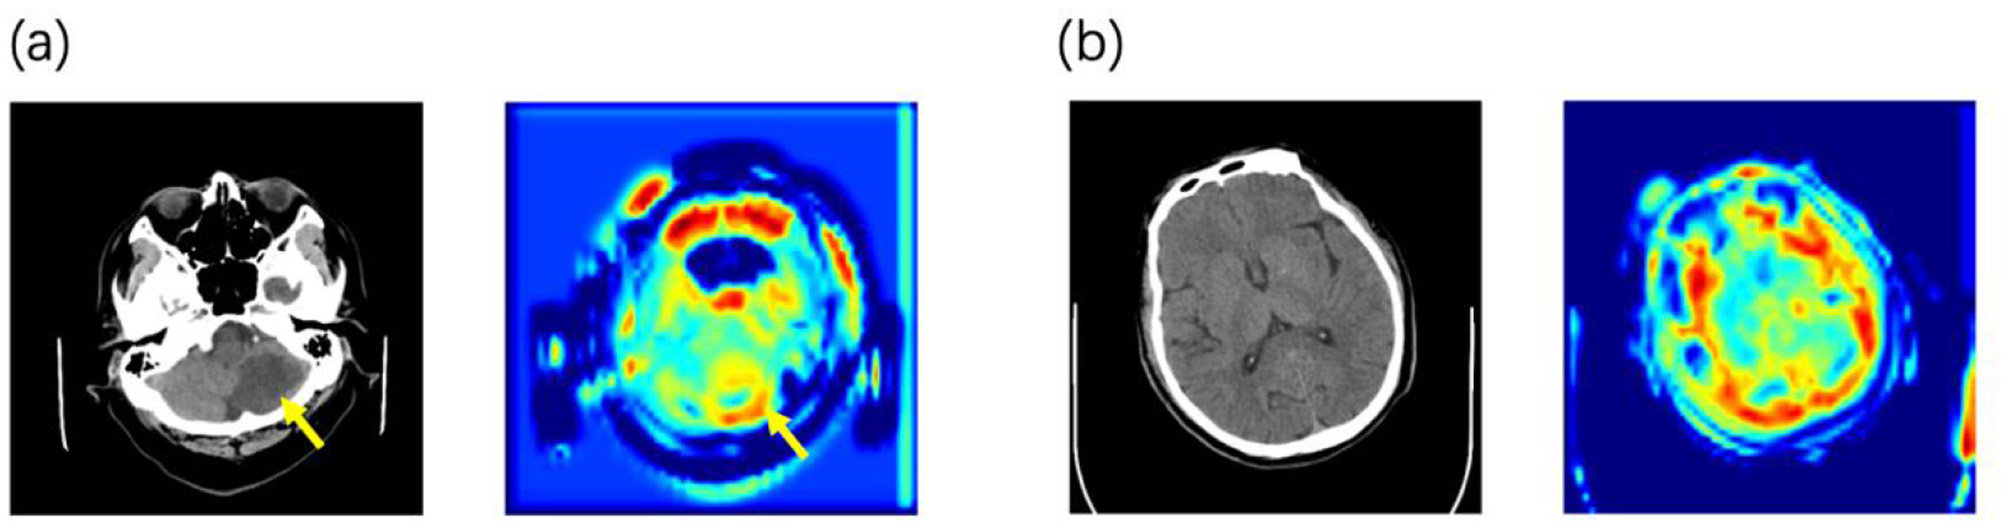

Using attention heatmaps, we visualized the anatomical regions utilized by the model. In cases with visible lesions (Figure 3a), the algorithm's focus correlated with the infarct area, confirming that the model effectively prioritized relevant pathological features. Notably, the model outperformed specialists in cases with low lesion visibility (Figure 3b), where it attended to specific brain regions that doctors might overlook. This suggests that deep learning attention maps could uncover subtle early indicators of HT.

Figure 3

Examples of the predicted NCCT scan images alongside its corresponding attention heatmaps (a) When lesions are detectable on CT, the model focuses its attention on the lesion area. (b) In the early stage before lesions are visible on CT, the model's attention is distributed across the entire brain parenchyma.